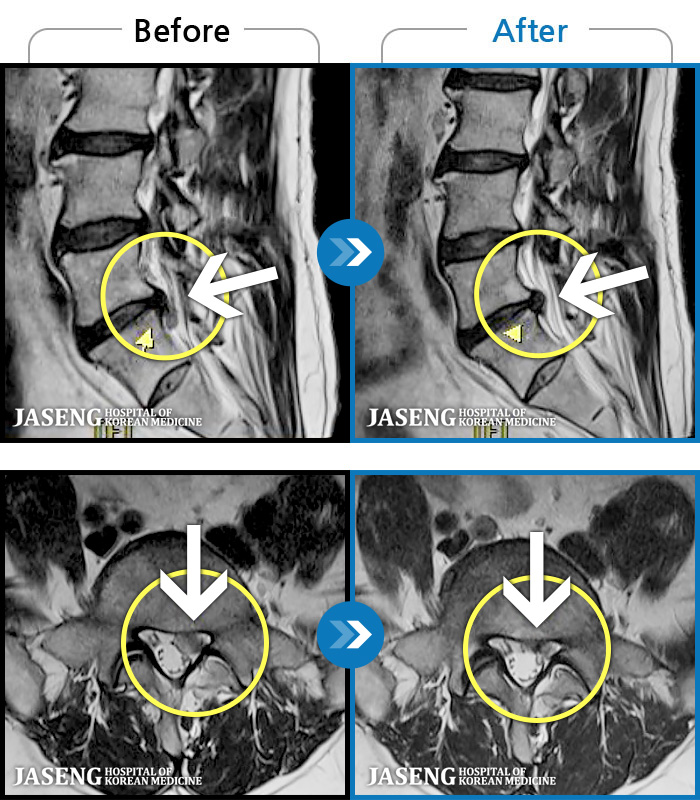

MRI ġ

1,299 MRI ũ ʸ Ȯϼ.